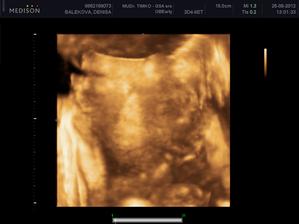

Nas anjelik Alex

Zatial este schovany v brusku ale uz coskoro sa z neho potesime aj nazivo 🙂) Lubime nasho Alexa uz od sameho zaciatku 🙂